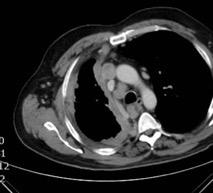

Signos radiológicos TC

Hallifax RJ et al. State-of-the-art: Radiological investigation of pleural disease Respiratory Medicine 2017

Nivel hidroaéreo o burbujas

Forma lenticular o elíptica Ángulos obtusos

> Grasa Extrapleural (60-80%)

Situación no gravitacional (no siempre)

Compresión de estructuras pulmonares

Límite muy bien definido Tabicación

Empiema

Engrosamiento de la pleura parietal 36/ 59 exudados (61%) 56% de D. paraneumónicos 100% de empiemas Especificidad.. 96%.

Exudado versus trasudado.

Aquino SL, et al. Pleural exudates and transudates: diagnosis with contrast-enhanced CT. Radiology 1994

Signo de la Pleura separada “Split pleural sign”

Capas pleurales de grosor uniforme realzadas por el contraste

No específico de empiema. Indica “exudado”. 68% de pacientes con empiema pleural.

Capas pleurales de grosor uniforme

Realce grasa extrapleural (30%)

> Grasa Extrapleural. (60-80%)

Kraus GJ. Split pleural sign. Radiology 2007